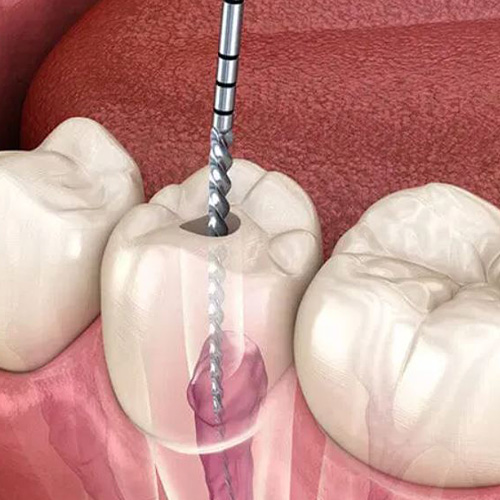

تمیز کردن و ضدعفونی کانالها

کانالهای ریشه با ابزارهای مخصوص تمیز و با مواد ضدعفونیکننده شستشو داده میشوند.

برداشتن پالپ عفونی

دندانپزشک با ایجاد سوراخی کوچک در تاج دندان، پالپ عفونی را خارج میکند.